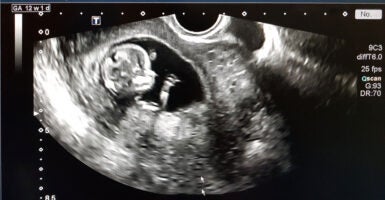

The chemical abortion pill regimen is a two-part process. The first pill, mifepristone (also known as RU-486 or its brand name, Mifeprex), causes the death of the unborn child by cutting off the hormone progesterone, which is required to sustain a pregnancy.

The second pill, misoprostol (brand name Cytotec), causes contractions to empty the uterus. The regimen is approved to be used for up to 70 days (10 weeks) into pregnancy.